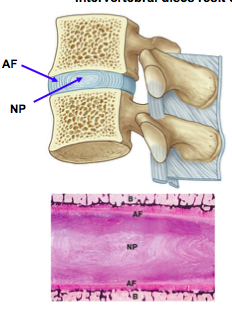

What structure exists inbetween vertebrae?

What happens to the intervertebral discs as you descend the vertebral column?

They increase in thickness to accomodate the greater weight/ force applied as you descend the vertebral column.

What happens when force is applied to the vertebral column?

This increases pressure in the nucleus pulposus.

The increase in pressure in the NP increases tension in the AF.

Increased tension in the AF pulls vertebral bodies together increasing stability and limiting further movement between vertebral bodies.